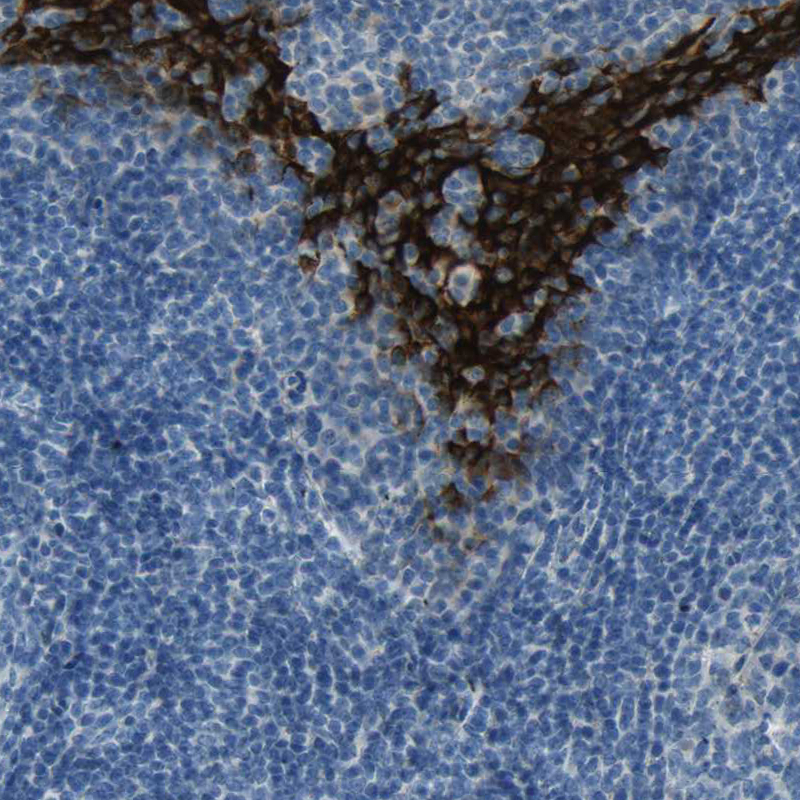

Immunohistochemistry analysis in human tonsil and kidney tissues using HPA009067 antibody. Corresponding SPINK5 RNA-seq data are presented for the same tissues.